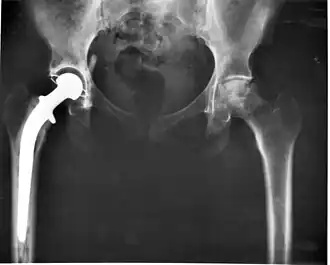

Бионические протезы

Бионические протезы объединяют протезирование и робототехнику, искусственными конечностями можно выполнять больше действий, чем обычными протезами, но бионические протезы рук не позволяют поднимать грузы более 5 кг, бионическими протезами рук невозможно пользоваться в темноте из-за отсутствия чувствительности, невозможно выполнить все движения доступные обычной руке[16], бионические протезы могут иметь дополнительные функции, работают от аккумулятора, который нужно заряжать, управляет протезом человек с помощью нервных импульсов с помощью микропроцессора.[17] Часто люди с бионическими протезами называют себя киборгами. Бионическими протезами пользуются только 10% инвалидов, так как они намного дороже, чем обычные протезы.[18]

Бионические протезы рук позволяет человеку, не только двигать искусственной рукой, но и осязать предметы которых он касается. Этот революционный проект был представлен на конференции, организованной Агентством перспективных исследований в области обороны Америки. После того, как исследователи из лаборатории прикладной физики в университете Джонса Хопкинса вживили электроды в мозг добровольца, парализованного травмой спинного мозга, он смог не только контролировать движение руки, но чувствовать, когда люди в лаборатории касались разных пальцев на протезе руки. В процессе тестирования бионической руки доброволец, даже с завязанными глазами смог определить, какого из пальцев руки-протеза касаются. Бионическими протезами и ранее можно было управлять при помощи сигналов мозга, однако только сейчас удалось добиться результата при котором сигналы с протеза обрабатываются мозгом. Этот эффект получен за счет электродов, имплантированных в сенсорную и двигательную кору головного мозга. Интегрированные в протез датчики определяют, когда к нему прикладывается давление, и преобразуют силу в электрические сигналы, которые передаются в мозг пациента.

Бионические протезы ног позволяют сгибать протез в колене и в стопе, быстрее передвигаться, чем с обычным протезом.[19]